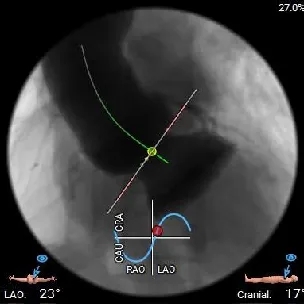

左右重叠体位:RAO 22° CAU 40° ,左冠切线位:LAO 23° CRA 17°;

工作体位

左右重合